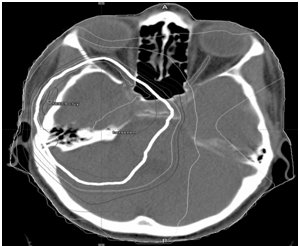

Optic Nerve and Chiasma Glioma Versus Radiation-Induced Chiasma Injury: is the Diagnosis Really that Easy?

Liselotte Aerts

Ophthalmology Research and Reports